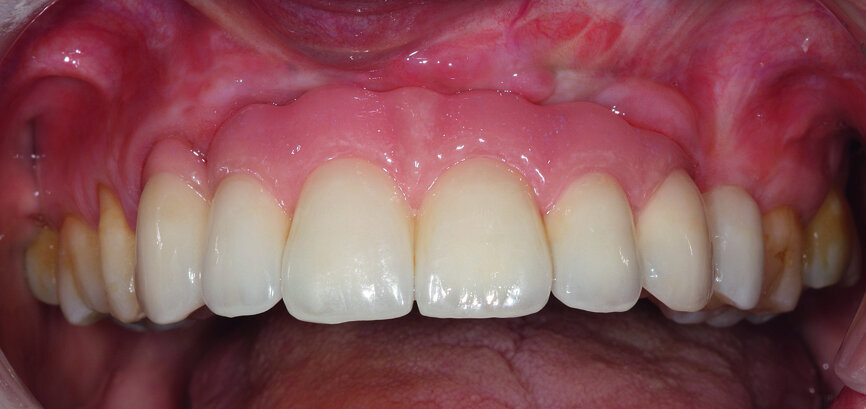

After six months, all of the parameters were validated. The final prosthesis was then fabricated as an exact copy of the validation prosthesis, but in a more durable material: zirconia for the framework and ceramic for the aesthetic material.

As with the titanium validation prosthesis, the framework and the coping for the right canine were scanned and transmitted to the machining centre. They were then tested on the working model (Figs. 32 & 33). After fitting of the zirconia framework, the ceramic was cast using the exact parameters validated by the resin prosthesis (MB Dentaltechnik, Figs. 34 & 35).

In the following step, the final prosthesis was installed and the correct occlusion verified: maximum intercuspation, protrusion and lateral excursion. The screw channels were filled with composite (Figs. 36 & 37).

The final cosmetic check-up, validated by the resin prosthesis, showed the lip support with the new extremely reduced false gingiva to be correct (Figs. 38 & 39). This was achieved owing to the bone graft.